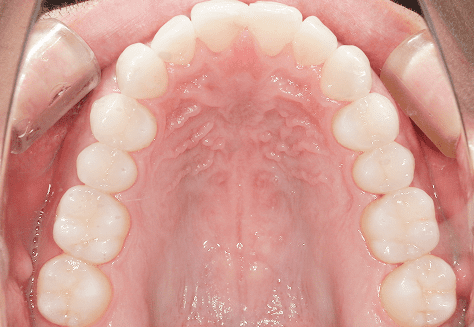

S.K

治療前

治療後

主訴

歯が重なっていて気になる。前歯が出ていて唇が閉じにくい。ハミガキがしにくい。

診断

上顎前突・叢生

年齢/性別

20代/男性

抜歯部位

上下第三大臼歯

使用装置

上下インビザライン

保定装置

上下ビベラリテーナー

基本料金

990,000円

1,100円×33回

治療期間

3年5カ月